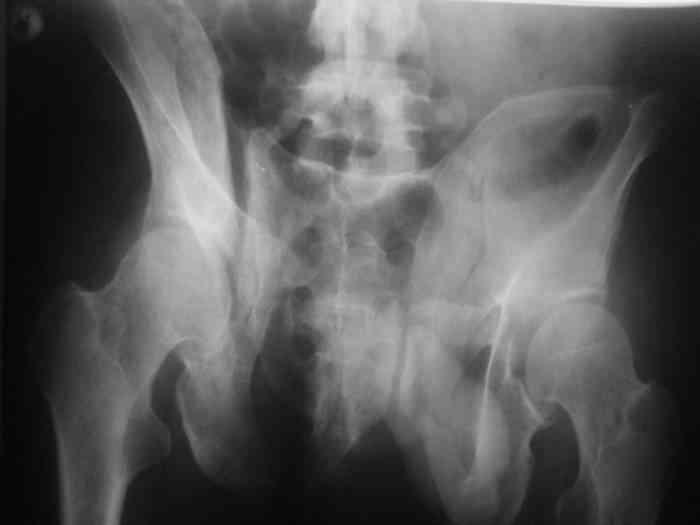

Остается только вариант закрытого аппаратного лечения. В аттаче положение отломков на вытяжении в прямой (АР) проекции. Для сравнения снимок до и во время вытяжения.

> Остается только вариант закрытого аппаратного лечения.. В аттаче

> положение отломков на вытяжении в прямой (АР) проекции. Для сравнения

> снимок до и во время вытяжения.

Первоочередно для тазовых операций важно обследование, снимки таза в инлет, оутлет и прямая

проекция.

На сравнительном снимке правый полутаз опустился

недостаточно, можно добавить вес и сделать все стандартные снимки.